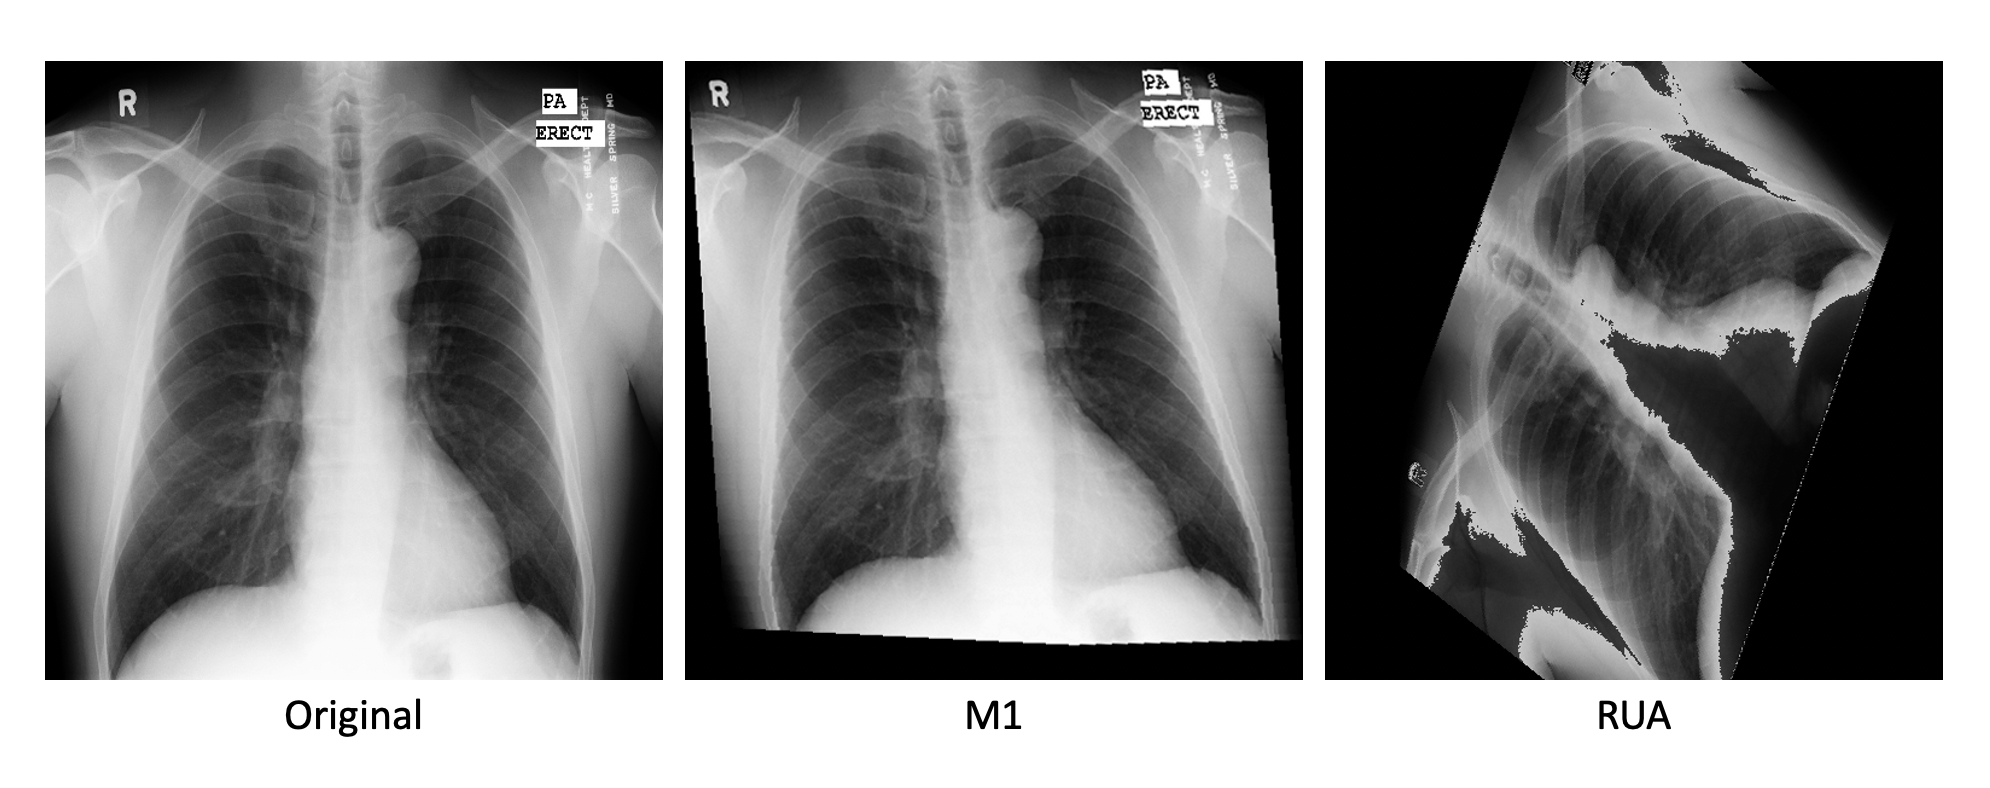

• Method 1 (M1) - Chest X-Ray transformations as proposed in aug1

• RUA - Our proposed transformations, applied at their maximum strength

While all of the baseline methods adhere to the domain availability heuristic (being comprised of mostly minor rotates, flips, stretching, etc.), our approach results in heavily distorted images that would never be found in a real clinical setting. A representative example can be found in Figure 6.

Refer to caption

Figure 6: A sample image under different augmentation strategies.